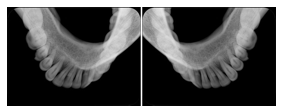

1. A patient in rural Canada visits a general ophthalmologist and is found to have diabetic macular edema. The general ophthalmologist would like to discuss the case with a retina specialist before performing laser surgery. A fluorescein angiogram is done with multiple retinal images taken in a timed series after an intravenous injection. The images along with a Structured Display are shared via a Health Information Exchange with a retina specialist in Calgary, who opens them using his Ophthalmology EMR software and consults via phone with the general ophthalmologist. Both physicians view the images in the same layout so the retina specialist can provide accurate guidance for treating the patient.

2. A patient in rural Iowa visits his primary care physician for management of diabetes. Three non-mydriatic (patient's eyes are not dilated) photographs are taken of the back of each eye, and forwarded electronically along with a Structured Display to an ophthalmologist in Iowa City. The ophthalmologist reads the photos in an agreed upon layout so there is no mistake about what portion of which eye is being viewed. The ophthalmologist is able to tell the primary care physician that his patient does not need to come to Iowa City for face to face ophthalmologic care, but that there is a particular view of the left eye that should be photographed again in 6 months.

Ophthalmic Retinal Study Structured Display

Figure OO-3. Ophthalmic Retinal Study Structured Display

3. A patient in rural Minnesota experiences sudden vision loss and goes to a general ophthalmologist, who acquires OCT images and forwards them electronically along with a Structured Display to a retina specialist six travel hours away. The retina specialist is able to view the images in the standard layout that he is comfortable with, and to confirm that the patient has a choroidal neovascular membrane. He determines that is would be worthwhile for the patient to travel for treatment.